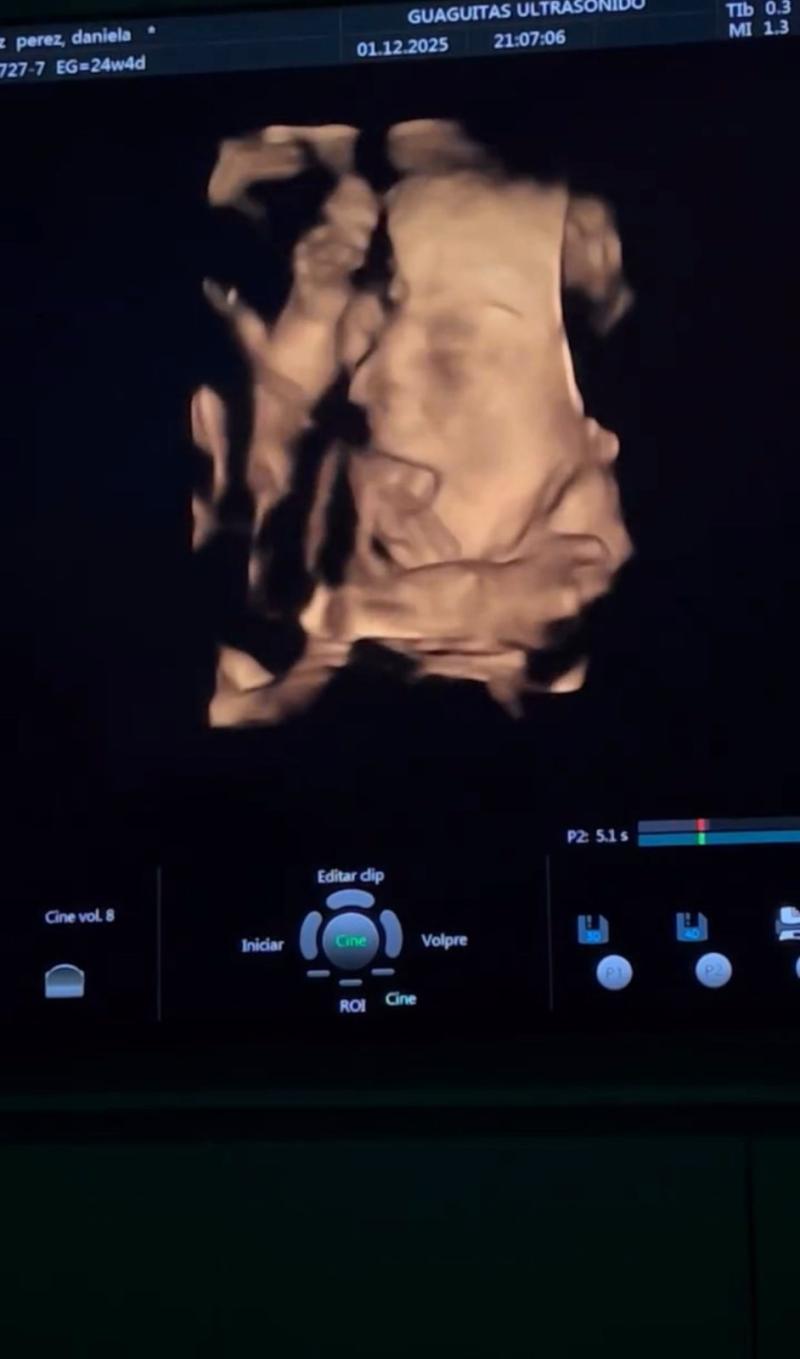

De hecho, ahora en su cuenta de Instagram compartieron un emocionante capítulo de este embarazo con sus seguidores. El músico y la actriz acudieron a la ecografía de su primer bebé en conjunto. "Hermosa experiencia", señalaron, emocionados por el proceso.

Camilo y Daniela mostraron varias imágenes del ambiente del recinto al que llegaron para la eco, en donde es posible pedir este examen en 5D, algo bastante novedoso. De hecho, en un extracto del registro, se logró apreciar el rostro del bebé en todo su esplendor.

En la descripción del video, la pareja escribió un mensaje que dio a entender cuál es el sexo del bebé que esperan. "Viendo a nuestro pepito. Un panorama bacán y un espacio muy cómodo para ir con la familia", dijeron.

Aunque no muchos lo notaron, ambos se refirieron al bebé como Pepito, lo que según sus seguidores es una pista de que el hijo que esperan es un niño.